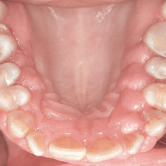

Frenillo labial hipertrófico

Un frenillo labial hipertrófico es una anomalía caracterizada por un frenillo labial superior grueso que puede causar problemas periodontales.

Los pacientes notan un pliegue de tejido muy grande entre su labio y su encía. Esto puede causar una separación entre los dientes delanteros y dificultar la higiene oral.

El tratamiento puede incluir una frenectomía para reducir el tamaño del frenillo